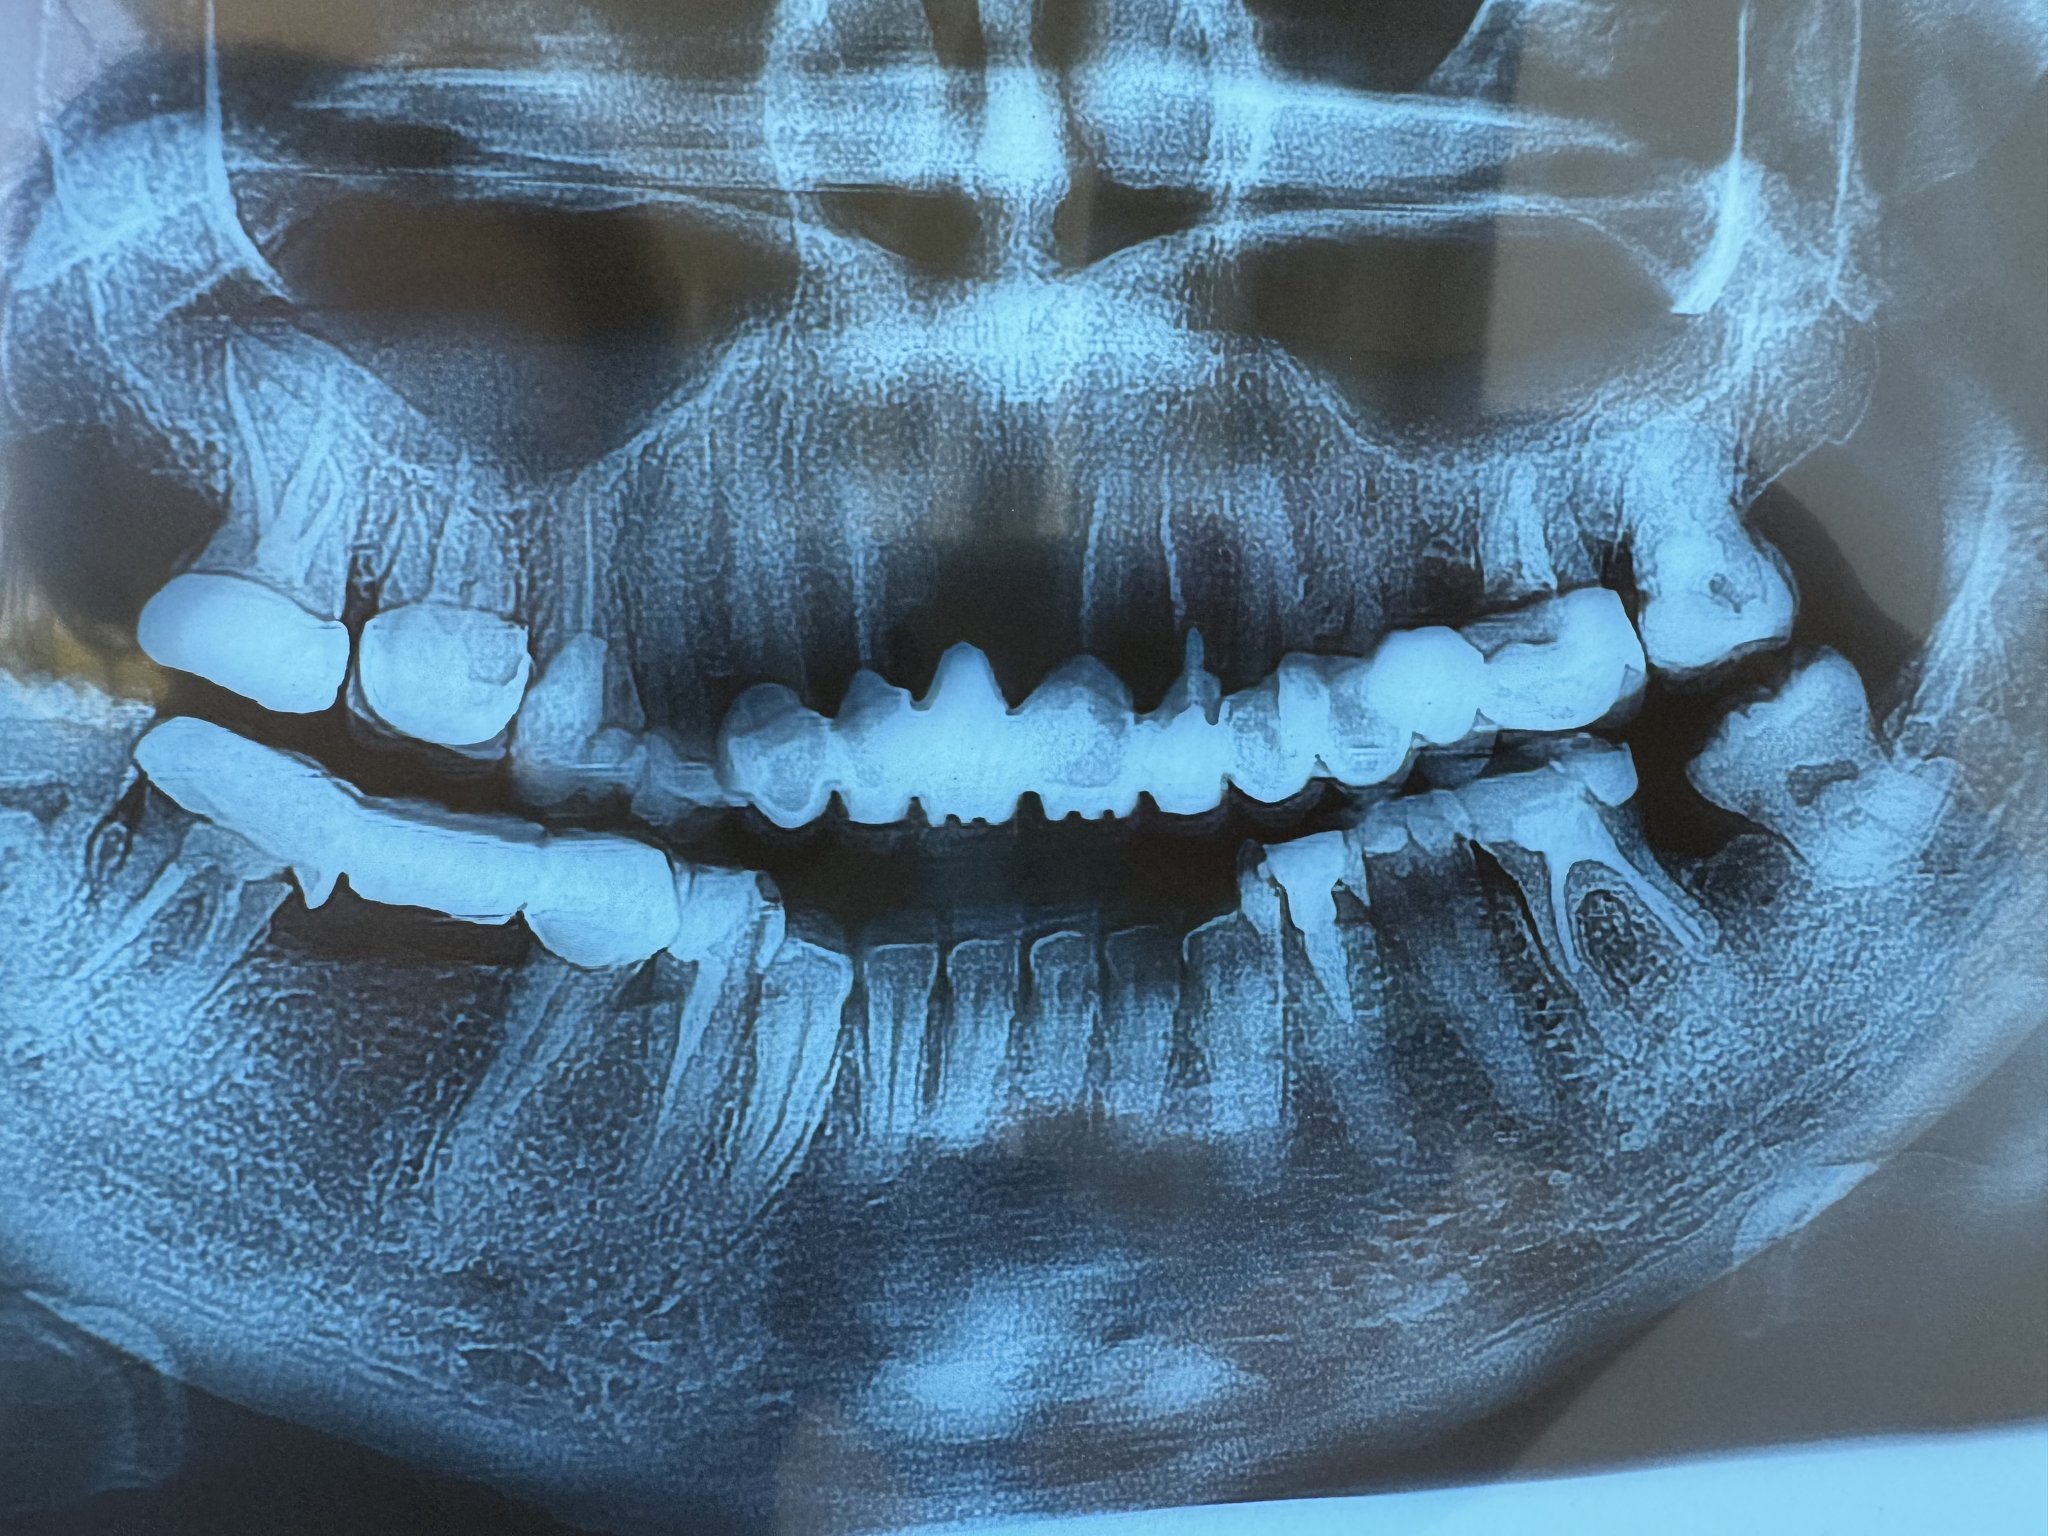

Извадих 3 мъдреца (всички от които ретинирани) и тъй като искам да започна ортодонтско лечение ми бе обяснено, че трябва да извадя и единственият здрав и нормално пробил (горен ляв) мъдрец.

Адекватно ли е от ортодонтска гледна точка?

ЛЧХ ми сподели, че не би извадил здрав зъб.

Трудно ми е, понеже другите ми леви молари са с обтурации поради кариес и пулпит и не ми е удобно при хранене.